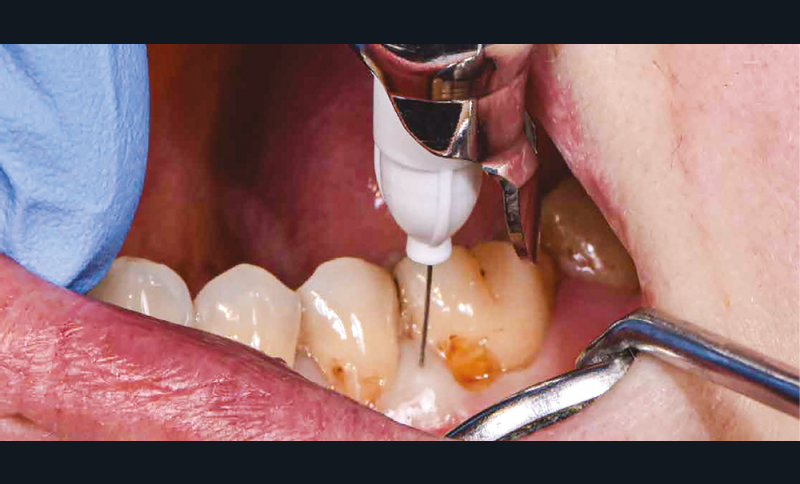

La première anesthésie se situe au niveau de la papille proximale entre 35 et 36. L’aiguille blanche de diamètre 0,30 mm et de longueur 16 mm est orientée de façon à avoir son repère légèrement décalé de la fenêtre du porte-aiguille (fig. 4). Ainsi, le biseau se pose à plat contre la muqueuse [1]. L’aiguille glisse doucement et de façon indolore dans la papille sur 2 mm et l’injection débute sans surpression sous contrôle électronique. Lorsque la papille montre une vasoconstriction suffisante, elle devient blanche et l’injection peut s’arrêter. La pièce à main s’oriente alors en direction de l’espace apical interdentaire avec un angle de 30 à 45° vestibulolingual (fig. 5). L’aiguille est mise en rotation pour pénétrer la corticale osseuse. Elle arrive ensuite dans la partie trabéculaire de l’os. Lorsque les deux tiers de l’aiguille sont sous la corticale, la rotation doit cesser et l’injection reprend avec une vitesse qui s’adapte électroniquement à la densité de l’os. Une demi-carpule d’articaïne 1/100 000 suffira à la restauration de ce secteur [2]. Le champ opératoire, le crampon, les ligatures sont placés (fig. 6) ; un crampon additionnel permet de descendre la ligature dans le sulcus de la 36 pour réaliser le soin vestibulaire (fig. 7). Les restaurations sont réalisées sans douleur (fig. 8) [3].